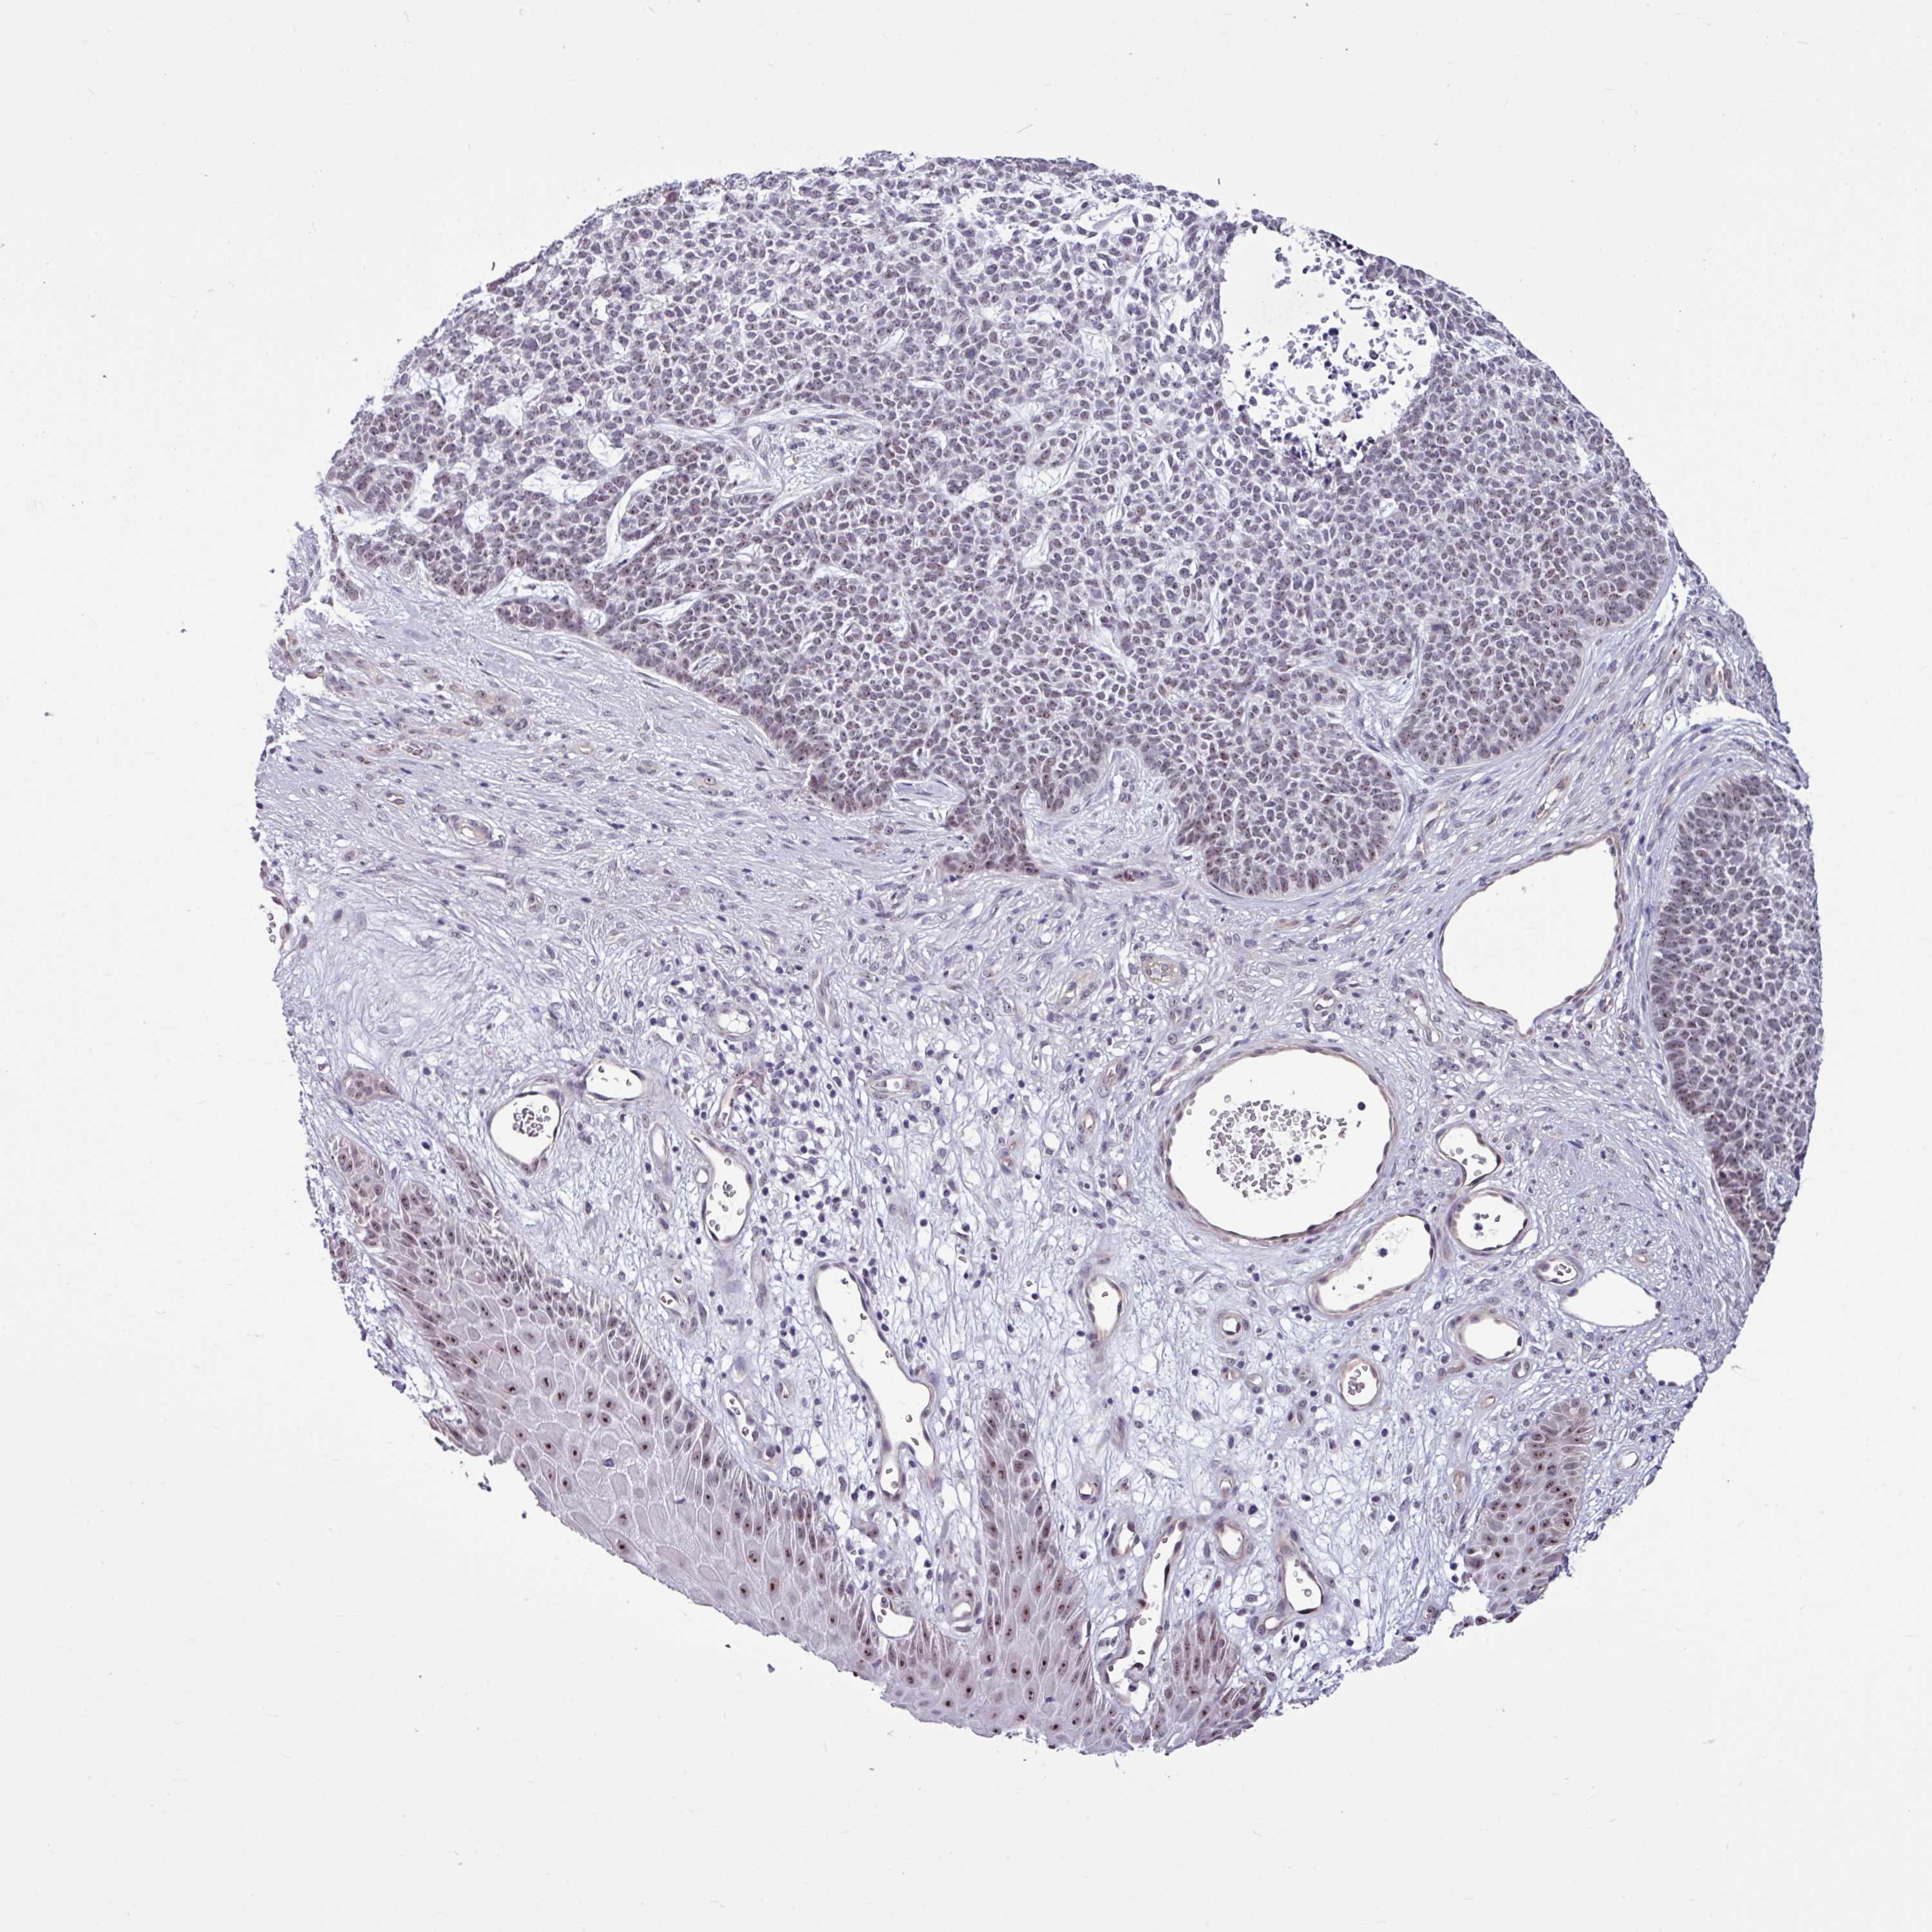

SKIN CANCER - Protein expressioni

A mouse-over function shows sample information and annotation data. Click on an image to view it in a full screen mode. Samples can be filtered based on level of antibody staining by selecting one or several of the following categories: high, medium, low and not detected. The assay and annotation is described here.

Each image is clickable and will lead to virtual microscopy that enables deeper exploration of all samples and also displays staining intensity scores, fraction scores and subcellular localization as well as patient and tissue information for each sample.

Antibody HPA052378

Staining

Medium

Intensity

Moderate

Quantity

75%-25%

Location

Cytoplasmic/membranous,nuclear

Squamous cell carcinoma, NOS